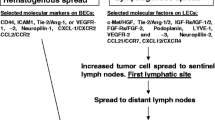

A deep understanding of these intricate interactions is crucial for devising treatments that can interrupt the metastatic process, such as drugs that block the enzymes cancer cells use to invade tissues, inhibit the growth of new blood vessels, or target the specific molecules and pathways cancer cells use to metastasize. These complicated pathways of cancer metastasis [7] may be depicted in Figs. 5 and 6.

Establishment of the lymph node (LN) pre-metastatic niche. Tumor-derived factors, including vascular endothelial growth factor (VEGF-A, VEGF-C and VEGF-D), extracellular vesicles, TGF-β and lysyl oxidase (LOX), induce an immunosuppressive microenvironment by recruiting macrophages, myeloid-derived suppressor cells (MDSCs) and regulatory T cells (Tregs). Proliferation of lymphatic endothelial cells (LECs) and fibroblastic reticular cells (FRCs) drives the production of LN factors such as chemokines (CCL19; CCL21; CXCL1, 2, 5, 8, and 12); TGF-β; matrix metalloproteinases (MMPs); indoleamine-2,3-dioxygenase (IDO); and nitric oxide (NO), which induce high endothelial venule (HEV) remodeling, stimulate lymphangiogenesis, and regulate tumor cells chemoattraction at metastatic stage. Permission to use this figure from Cellular and Molecular Life Sciences, Gillot et al., 2021, falls under Creative Commons CC BY 4.0. Gillot L, Baudin L, Rouaud L, Kridelka F, Noel A (2021) The pre-metastatic niche in lymph nodes: formation and characteristics. Cell Mol Life Sci 78 (16):5987–6002. https://doi.org/10.1007/s00018-021-03873-z

Understanding the molecular events leading to the formation of a pre-metastatic niche [Fig. 6] in SLNs may explain the conundrum of a SLN being reactive against cancer and as an incubator for cancer growth. A more detailed account of the pre-metastatic niche may be found in several reviews [76, 83, 84]. Once these molecules are targeted, therapies may be developed to disrupt the cancer metastasis process and potentially prevent cancer metastasis to distant organs.

VEGF A, B, C and E bind with their respective receptors and cause proliferation of blood vessels while VEGF C and D are involved in lymphangiogenesis [90] as shown in Fig. 6. Based on their extensive studies of lymphangiogenesis and cancer metastasis, Detmar and Hirakawa have concluded that VEGF-C and the VEGFR-3 axis play an important role in the lymphangiogenesis of cancer metastasis to allow cancer cell to enter through the lymphatic vessels [77]. Cancer-induced lymphatic vessels by lymphangiogenesis may become dilated [91]. In the lymphatic vessel cancer cells may be trapped at the valve with subsequent growth within the lymphatic vessel [92]. Cancer cells may extravate through the wall of the lymphatic vessel and invade into the adjacent soft tissue (Fig. 2).